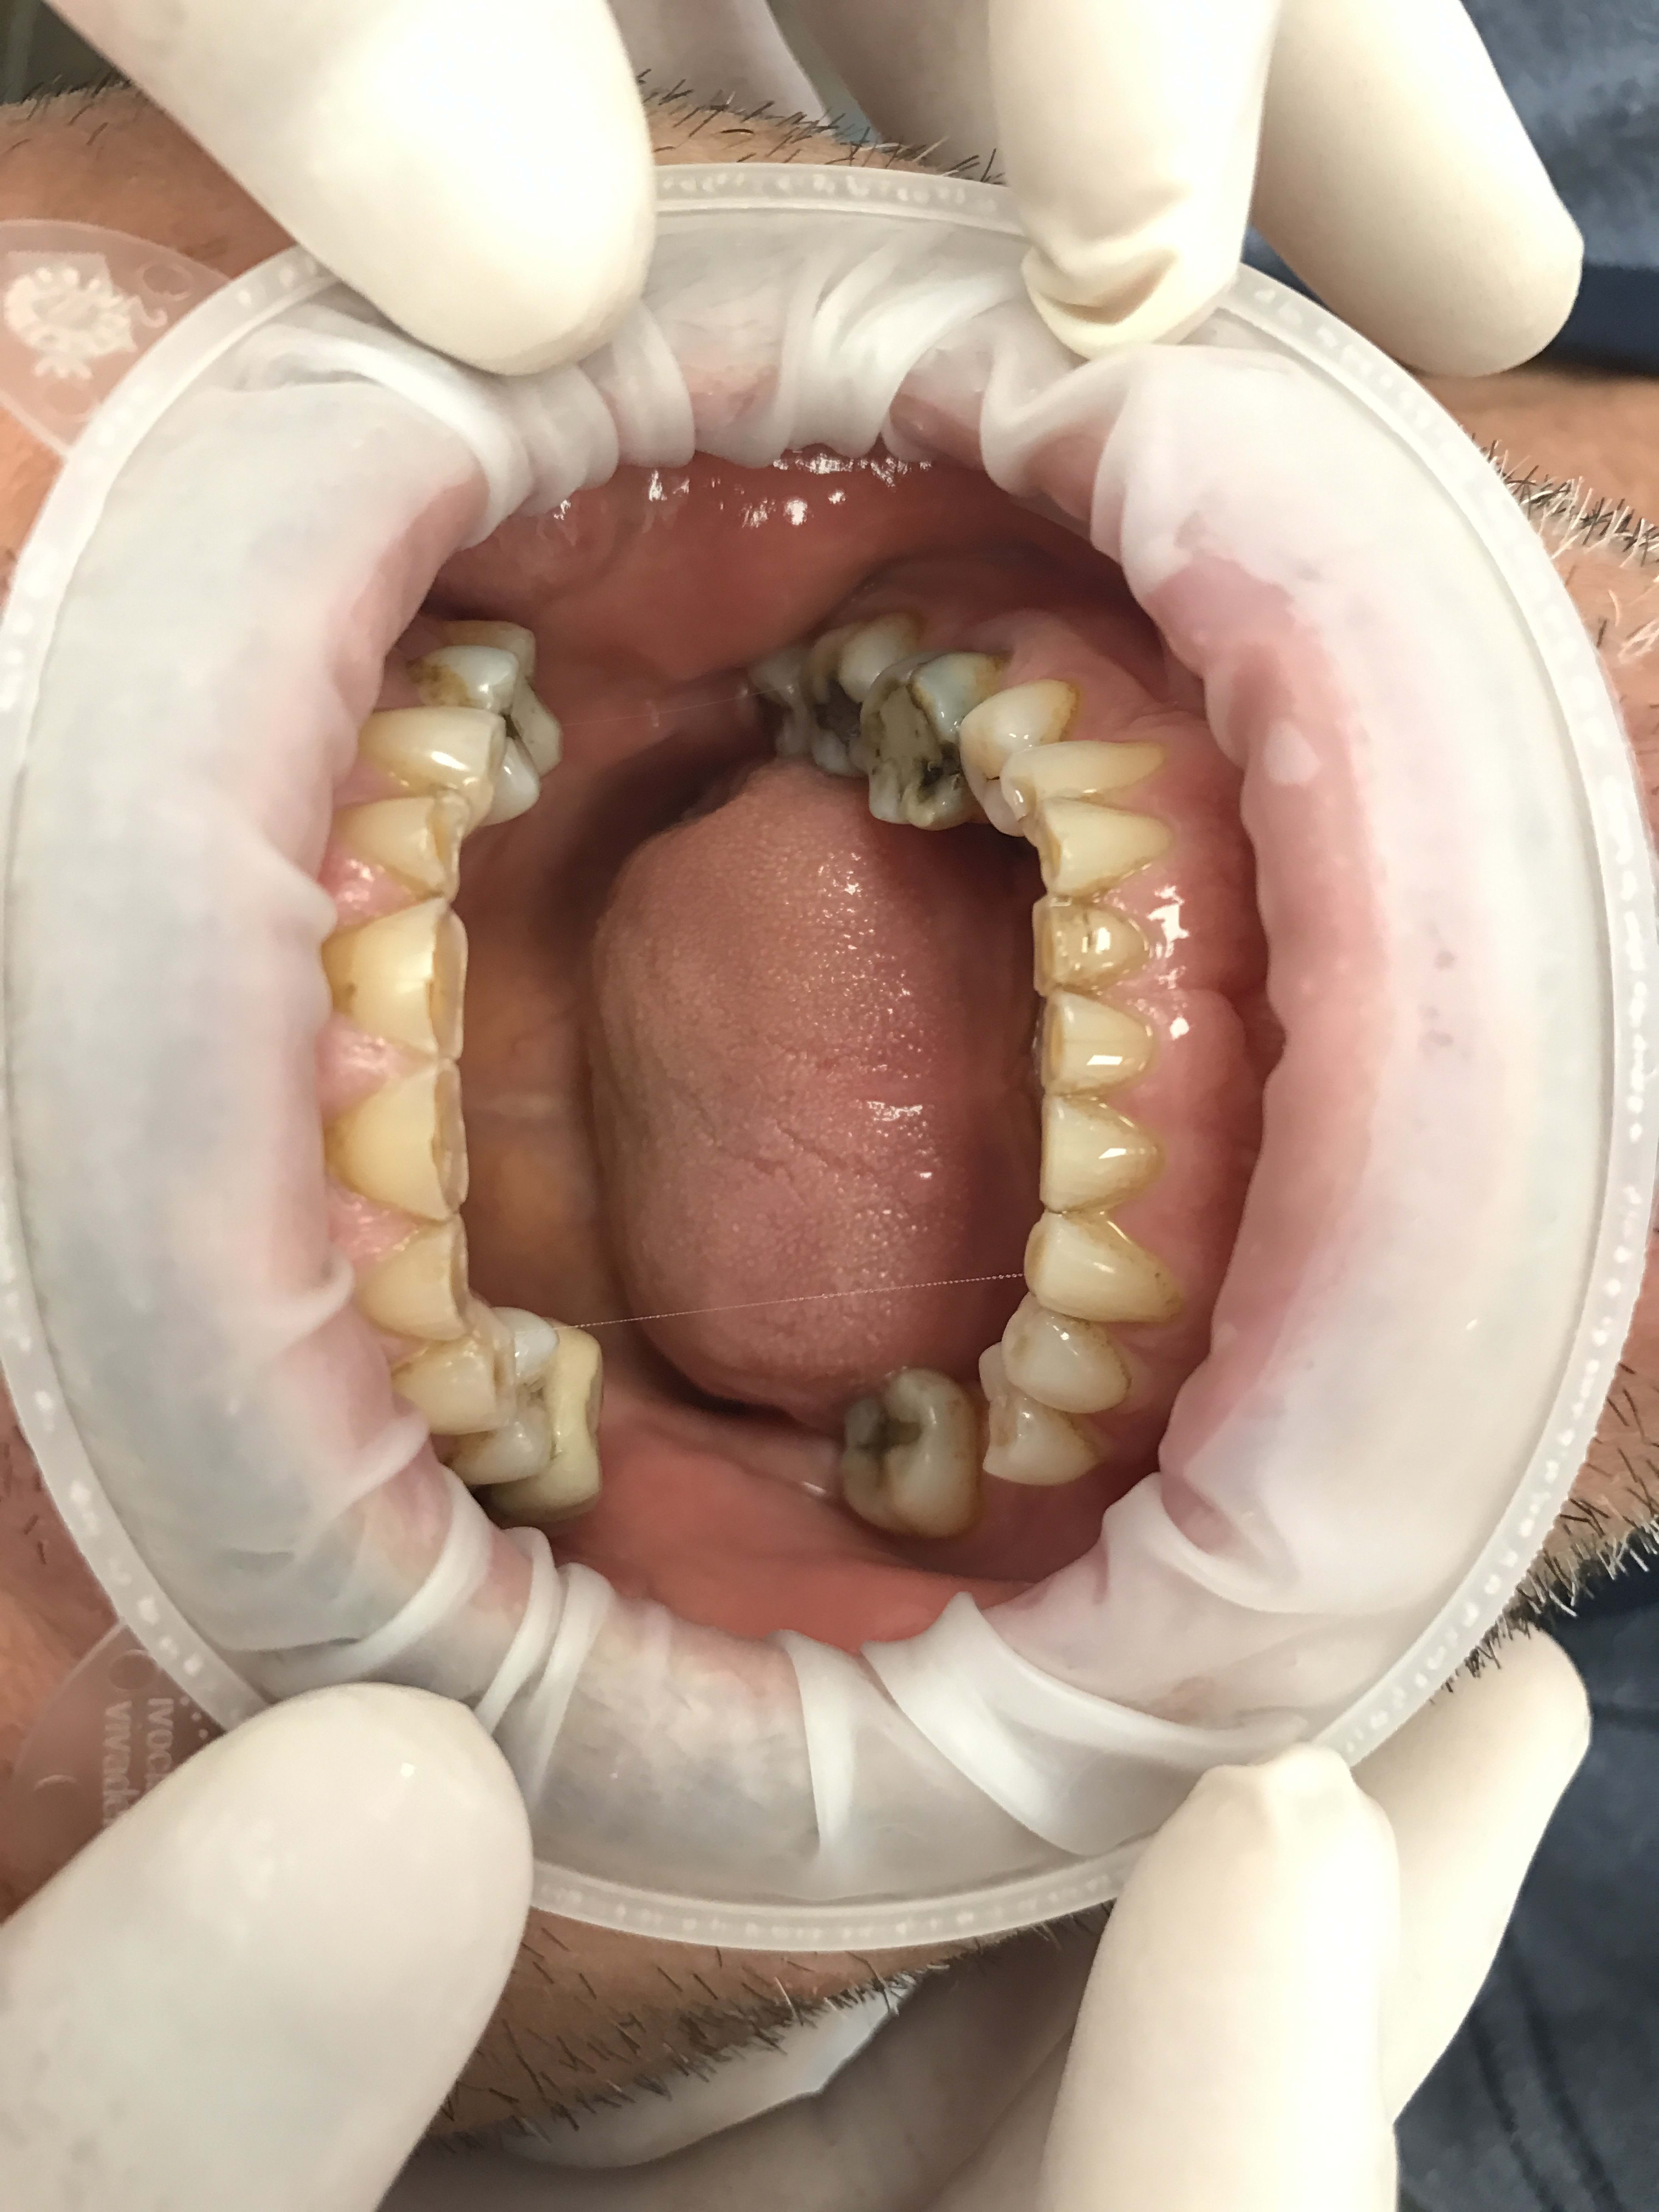

Restauration globale sur un patient qui bruxe?

Cela fait bien longtemps qu'il bruxe et a usé toutes ses dents, n'a plus de calage.

Il y a un retraitement à faire et deux implants à poser (26 46).

Je pensais faire suite au rte et à la pose des implants un wax up mock up avec facettes en antérieure et table top/couronnes en postérieur, et augmentation de la dvo de plusieurs mm.

Il ne va pas arrêter son bruxisme comme pas enchantement après s'être arrêté de travailler. Et la 26 et 46 ont été perdues par fêlures fractures je présume.